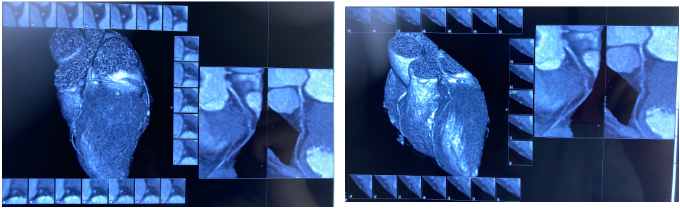

IVUS-1

远段直径2.2*2.4mm

对角支处局限血肿

IVUS-2 预扩张后小夹层和血肿

Dia开口

Dia近段

LAD闭塞段

LAD近段

LAD开口